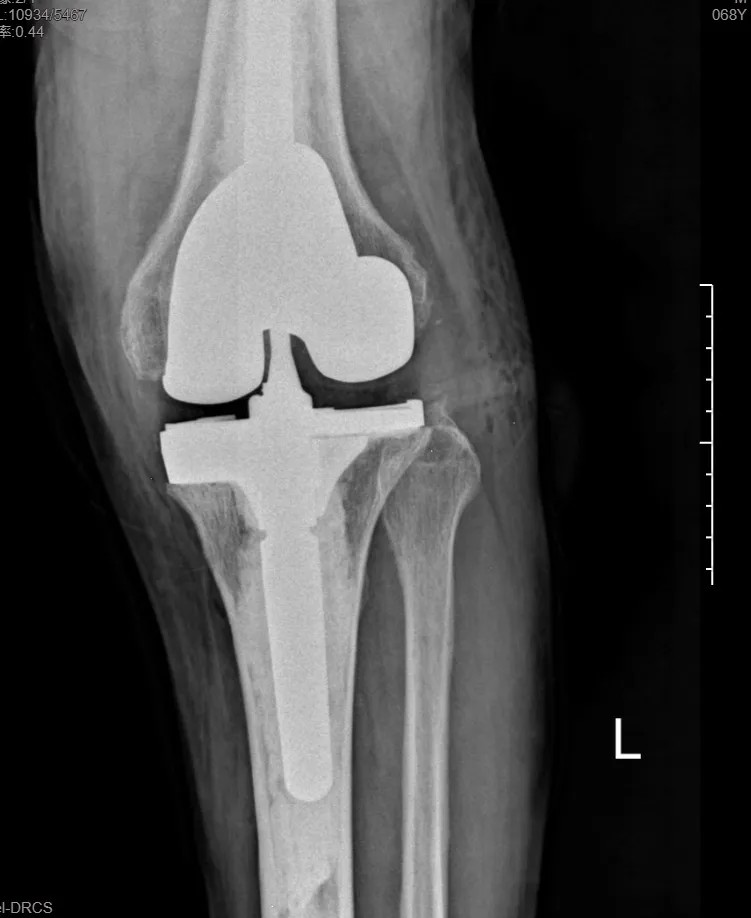

本次手術(shù)的核心,是采用了Evolution® ECCK膝關(guān)節(jié)翻修系統(tǒng)。該系統(tǒng)專為應(yīng)對(duì)翻修手術(shù)中常見的嚴(yán)重骨缺損、韌帶功能不全等極端復(fù)雜情況而設(shè)計(jì)。

其模塊化的組件提供了前所未有的靈活性,就像一套高精度的“工程套件”,允許醫(yī)生在術(shù)中根據(jù)實(shí)際骨缺損情況,自由組合不同尺寸的墊塊、延長桿等部件,實(shí)現(xiàn)關(guān)節(jié)線和力學(xué)穩(wěn)定性的個(gè)體化重建。

尤為重要的是,該系統(tǒng)保留了內(nèi)軸型假體的設(shè)計(jì)哲學(xué),在重建關(guān)節(jié)穩(wěn)定性的同時(shí),努力模仿了人體膝關(guān)節(jié)自然的運(yùn)動(dòng)方式(內(nèi)軸穩(wěn)定性、外側(cè)活動(dòng)性),旨在讓患者術(shù)后不僅能走,還能走得更舒適、更自然。

集多項(xiàng)前沿科技于一體的精準(zhǔn)手術(shù),帶來了令人欣喜的結(jié)果。術(shù)后第一天,在醫(yī)生指導(dǎo)下,張先生便能夠借助助行器下地站立、邁步行走。

“感覺非常好!膝蓋那里終于不痛了,而且自己能控制它了。”張先生的喜悅之情溢于言表??焖俚墓δ芑謴?fù),極大地增強(qiáng)了他的康復(fù)信心。